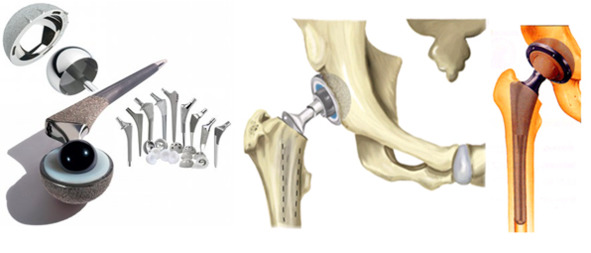

- Виды дентальных имплантатов

- Имплантат в форме корня зуба